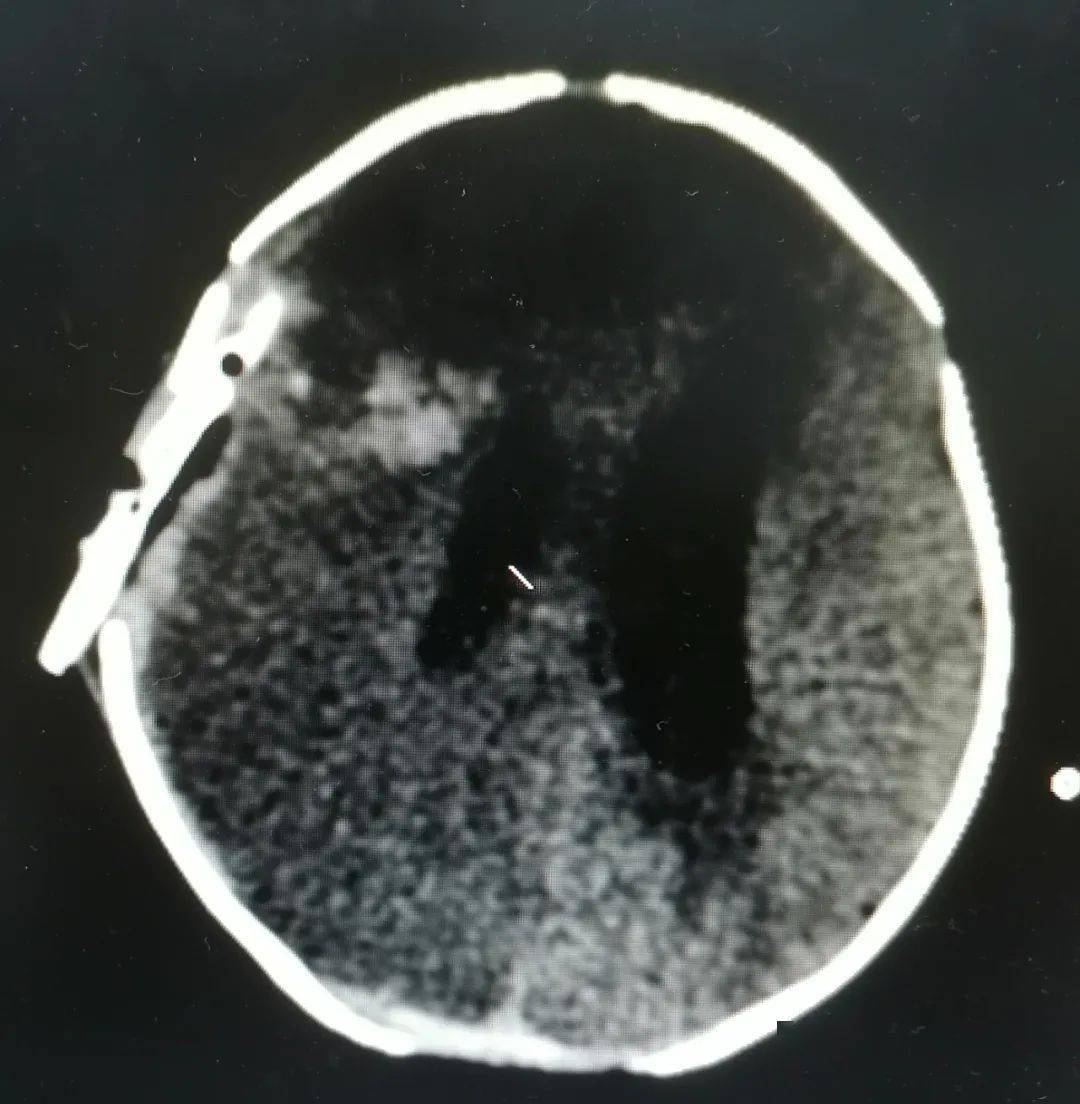

40天婴儿颅内出血梧州市工人医院神经外科联合儿科紧急救援